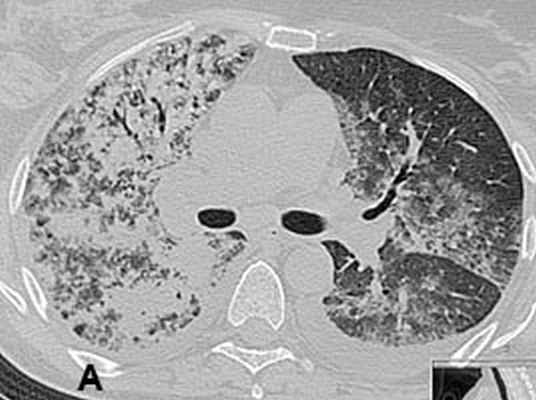

Госпитализирована в ЦКБ Гражданской авиации с диагнозом: очаговая пневмония. Анализ крови при поступлении: гемоглобин 82 г/л, лейкоциты 20х109/л, СОЭ 80 мм/час. При КТ грудной клетки 24.12.07 подтвержден диагноз двусторонней полисегментарной пневмонии (рис. 1). Назначен роцефин 2,0 г/сут. Осмотрена фтизиатром, который исключил специфическое поражение легких.

Рис 1. КТ органов грудной клетки с реконструкцией от 24.12.2007: двусторонняя сливная пневмония. Видны зоны инфильтрации легочной ткани.

А – фронтальная плоскость; Б, В – горизонтальная плоскость. Через 2 недели при контрольной рентгенографии легких, а затем при КТ органов грудной клетки от 11.01.08. выявлена отрицательная динамика: тотальная пневмония с элементами деструкции справа, сливная нижнедолевая пневмония слева, реактивный плеврит (рис. 2). С подозрением на тотальную двухстороннюю септическую деструктивную пневмонию 11.01.08 больная была переведена в отделение реанимации центра гнойно-септической хирургии НМХЦ им. Н.И.Пирогова.